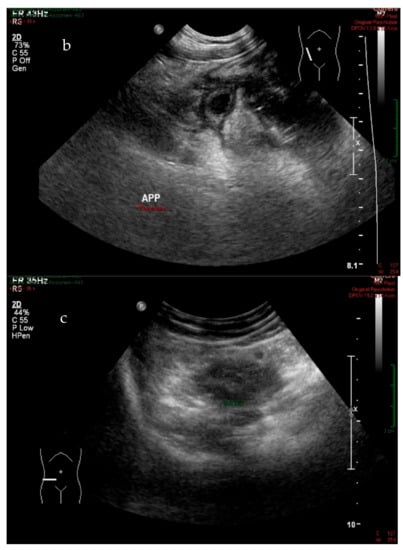

2.3. US Procedure